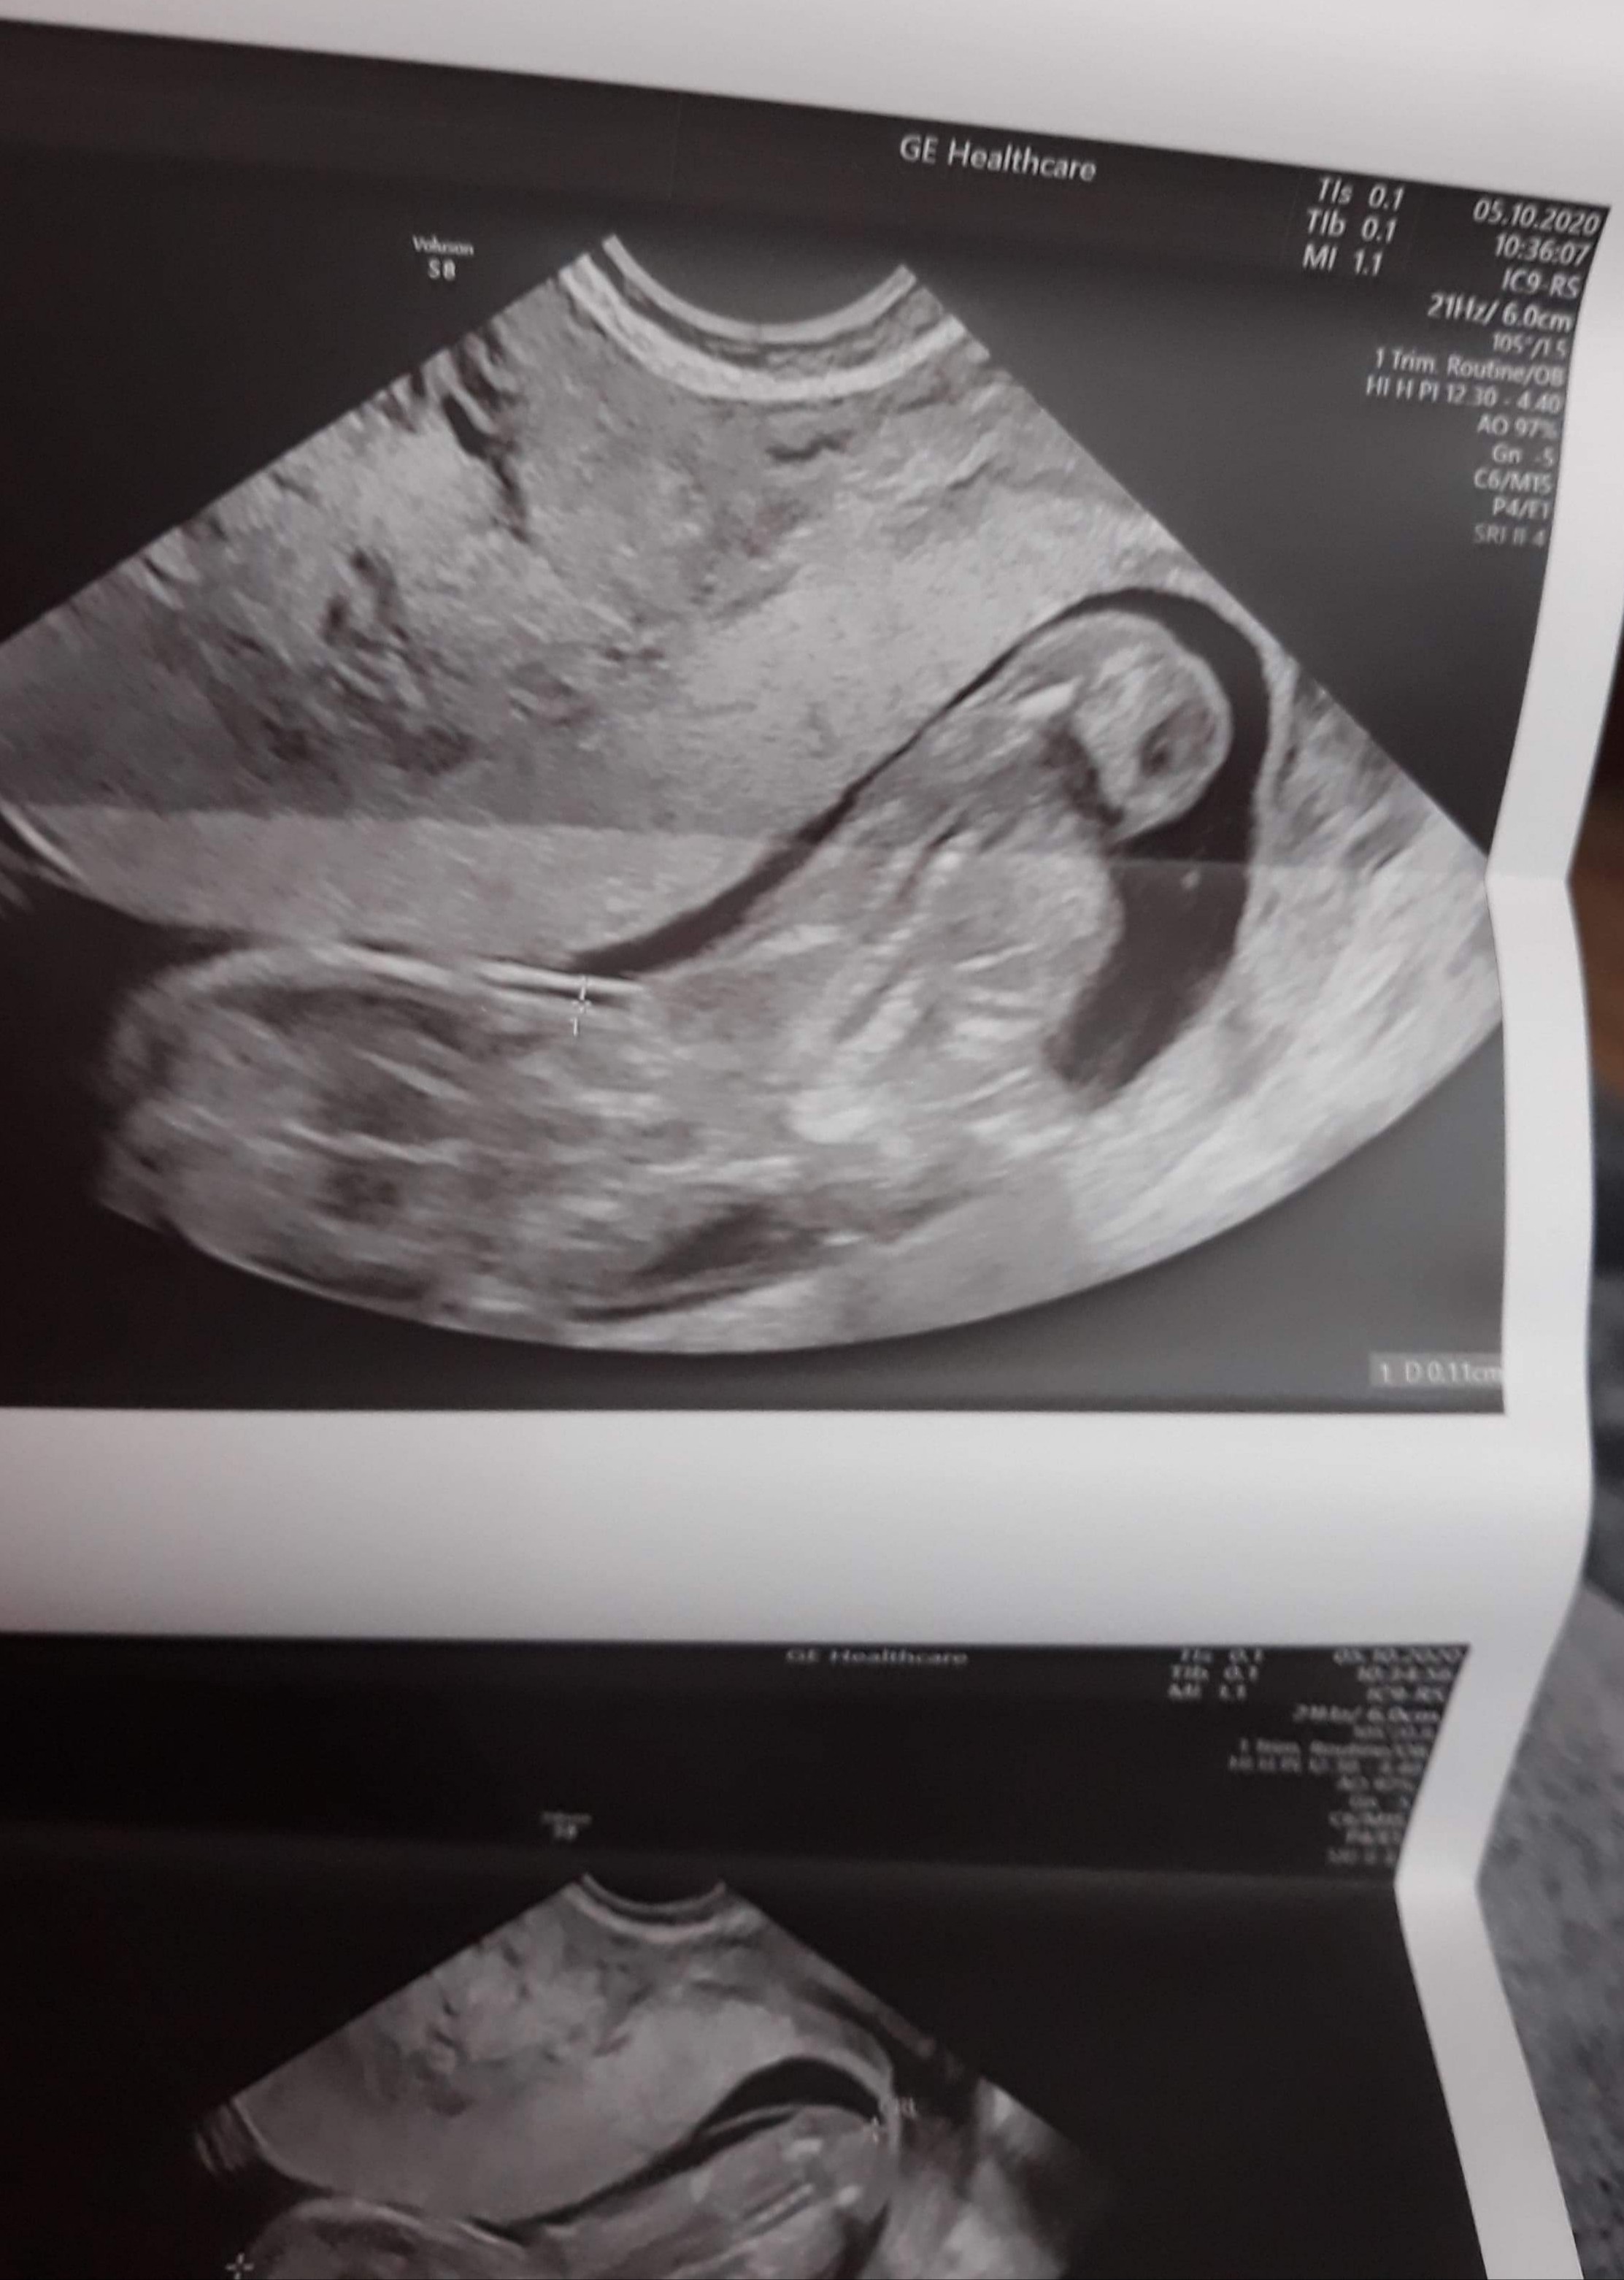

Usg w 13 tc

Witam , wiem , że to może głupie pytanie , ale to moja 1 ciąża i się wszystkim przejmuję. Dlaczego te usg jest takie dziwne , zamazane ? Wogóle nie widać kształtów dziecka. Czy któras też tak miała?

Tylko takie zdjęcie masz ? Wygląda trochę jakby była próba łapania przezierności, ale dziwnie nie bokiem tylko tyłem, to drugie chyba jest z pomiarem crl i wygląda na pierwszy rzut oka lepiej, ale też bez szału. Dzidzuś się mocno ruszał? Słabe to zdjęcie, a to ważne usg, masz opis taki porządny ze wszystkimi pomiarami itd.? Jak nie to może powtórz u kogoś z lepszym sprzętem...